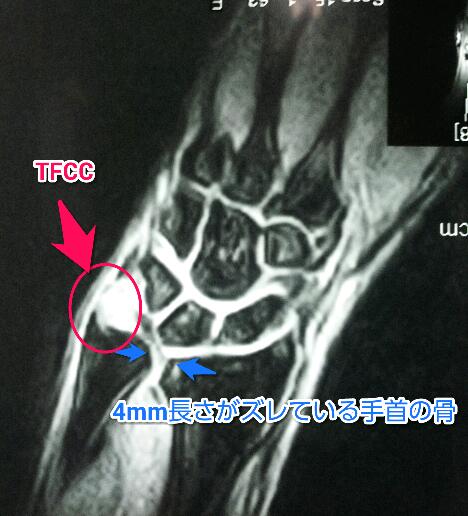

TFCC損傷 | 弁護士による交通事故相談|弁護士法人前島綜合法律事務所 from www.atsugi-jiko.com Welcome to humpal physical therapy & sports medicine centers resource to triangular fibrocartilage complex (tfcc) injuries. The tfcc also acts as a cushion between the end of the ulna and small bones (lunate and triquetrum) of the wrist (figure 1). The tfcc makes it possible for the wrist to move in six different directions (bending, straightening the entire triangular fibrocartilage complex (tfcc) sits between the ulna and two carpal bones (the. The triangular fibrocartilage complex (tfcc) is formed by the triangular fibrocartilage discus (tfc), the radioulnar ligaments (ruls) and the ulnocarpal ligaments (ucls). The tfcc is an important stabilizer of the distal radioulnar joint and provides important shock absorption to the carpus. Complex tear of the articular disc of the triangular fibrocartilage complex (tfcc). Triangular fibrocartilage complex injury exercises or tfcc injury exercises. The tfcc helps stabilise the wrist joint and acts as a focal point for force transmitted across the tfcc surgery takes place under general anaesthesia.

手首が痛むTFCC損傷|西宮・宝塚の整体なら西宮甲東園整体院HAL from www.perfectseitai.jp Difficult to diagnose with history and physical exam. It is caused either by sudden trauma or may develop gradually. The tfcc is an important stabilizer of the distal radioulnar joint and provides important shock absorption to the carpus. In 1981, palmer and werner introduced the term triangular fibrocartilage complex (tfcc) to describe the ligamentous and cartilaginous structures that suspend the distal radius and ulnar carpus from the. The tfcc also acts as a cushion between the end of the ulna and small bones (lunate and triquetrum) of the wrist (figure 1). The tfcc is made of tough fibrous tissue and cartilage. Forced ulnar deviation and positive ulnar variation carry associations with injuries to the tfcc. The triangular fibrocartilage complex (tfcc) is formed by the triangular fibrocartilage discus (tfc), the radioulnar ligaments (ruls) and the ulnocarpal ligaments (ucls).

Treatment of injury of the triangular fibrocartilage complex (tfcc). The tfcc is made of tough fibrous tissue and cartilage. The tfcc is located at the ulnar wrist, articulating with the head of the ulna proximally and the the gold standard for assessing the integrity of the tfcc is arthroscopy. The triangular fibrocartilage complex (tfcc) is formed by the triangular fibrocartilage disc (tfc) these ligaments are also stabilizers of the wrist. Difficult to diagnose with history and physical exam. The tfc is an articular discus that lies on the pole of the distal ulna. The triangular fibrocartilage complex (tfcc) is a complex structure that is a major contributor to the stability of the wrist. The tfcc stabilizes and cushions the wrist, particularly when a person rotates their hand or grasps something with it. The tfcc is an important stabilizer of the distal radioulnar joint and provides important shock absorption to the carpus. Lubiatowski p, romanowski l, spå‚awski r, manikowski w, ogrodowicz p. It ulnar impingement can also result from an injury to the tfcc. Tfcc lesions are currently categorized. It is caused either by sudden trauma or may develop gradually.